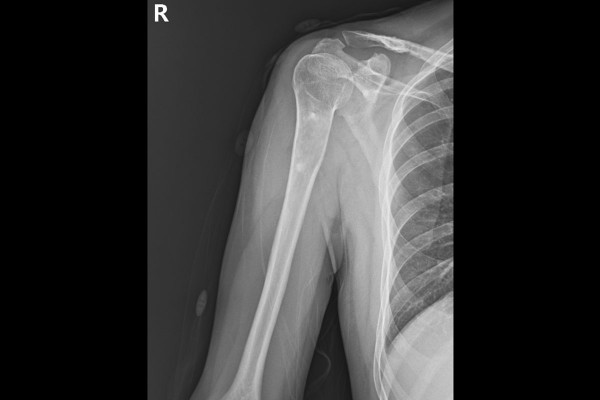

수술 후 촬영한 X-RAY에서 수술 후 종양이 거의 다 잘 제거된 것이 확인됩니다.

환자분의 경우 진단이 참 어려웠던 케이스인데, 돌이켜보면 단순 골낭종이 있던 자리에 20년 전에 골절이 발생하면서, 골절이 회복되는 과정에서 뼈의 일부가 괴사 되었고, 딱딱한 조직이 안에 생기면서 섬유화된 괴사조직들이 뼈 안을 채우고 있던 것으로 판명됩니다.